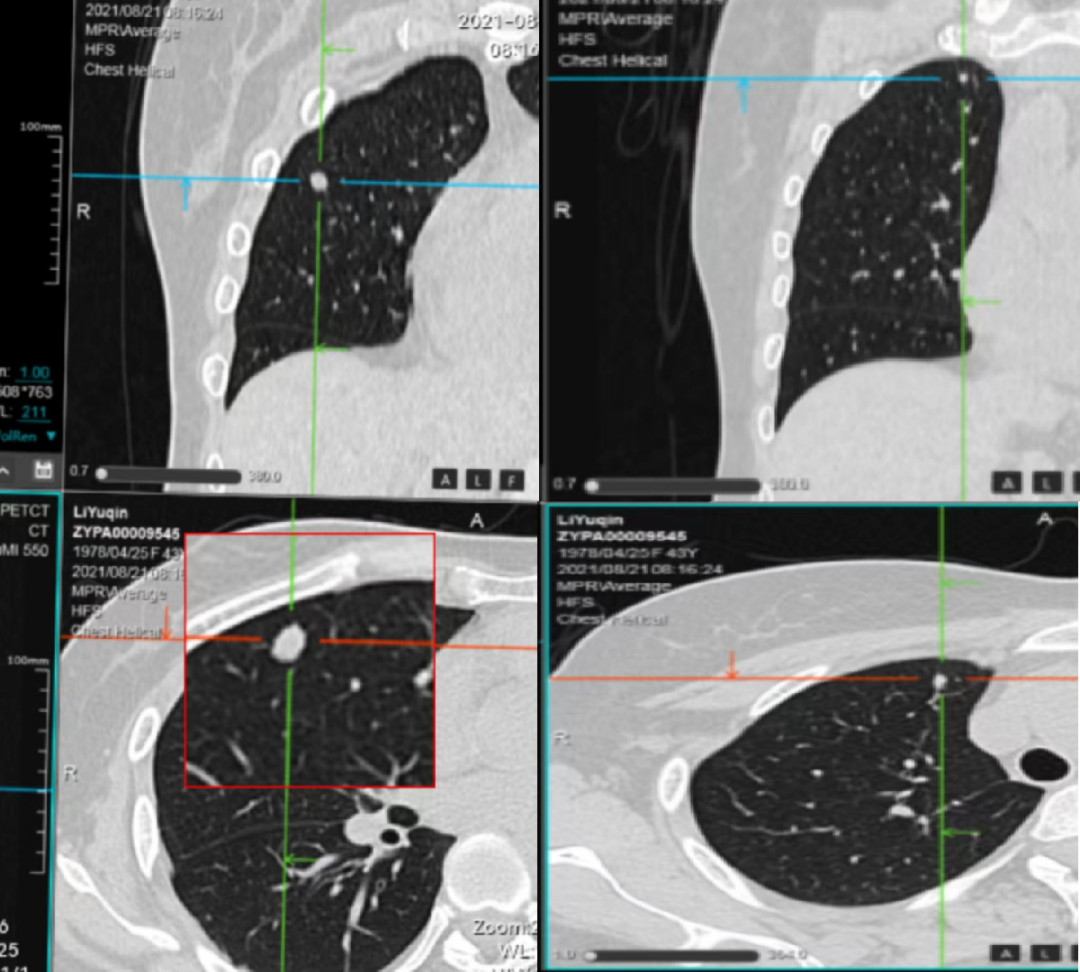

√ 临床试验mFOLFOX+西妥昔单抗,要求入组:条件肿瘤直径达到1cm。

★ 2021-8-12观察至2021-10-8 未行化疗等治疗,行强化CT对比:大者(0.8cm×0.6cm)至(0.9cm×0.7cm),仍无法入组。

▲2021-10-8 检查项目:胸部CT平扫(普+特)、盆腔CT强化+平扫(普+特)和胸部CT强化+平扫(普+特)的影像表现与印象

▲2021-11-25 检查项目:胸部CT平扫(普+特)、上腹CT平扫(普+特)、盆腔CT强化+平扫(普+特)、上腹CT强化+平扫(普+特)和胸部CT强化+平扫(普+特)的影像表现与诊断意见

√ 2021-11-25 复查CT达到入组标准,于2021-12-2 开始入组临床试验mFOLFOX+西妥昔单抗。

2021-4-12 CT复查发现右肺中叶0.5cm×0.2cm结节,2021-8-12(0.8cm×0.6cm)观察至2021-10-8(0.9cm×0.7cm),观察至2021-11-25(1.0cm×0.7cm)达到入组标准;